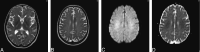

Hypoxic ischemic encephalopathy may cause early deep white matter abnormalities on MR imaging that usually progress to include gray matter and basal ganglia change. Toxic leukoencephalopathy due to heroin inhalation predominantly causes cerebellar and posterior cerebral radiologic change. Both conditions rarely present clinically and radiologically in a delayed manner with subsequent recovery. We report a case of reversible delayed posthypoxic/toxic leukoencephalopathy with no clinical or radiologic evidence of gray matter insult.